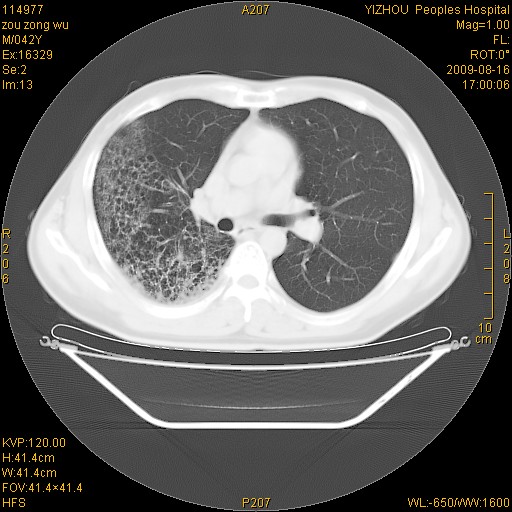

以下是引用zjzjr在2009-8-17 10:42:00的发言:[br]右侧间质性肺炎伴纤维化,右肺下叶肺囊肿伴感染(不除外外伤后引起),右肺野及胸壁软组织\\肝内见多发斑点状,中枪了吧.右侧胸膜肥厚\\粘连.